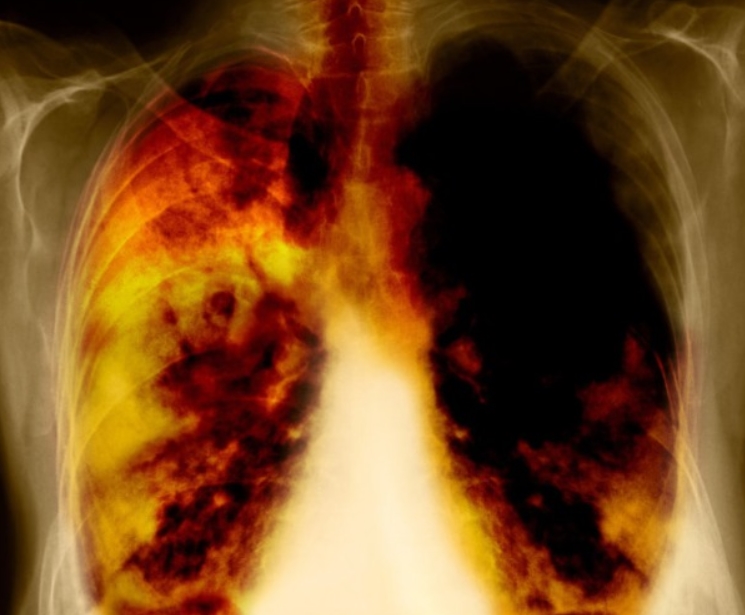

만성 폐쇄성 폐질환은 숨이 드나드는 길이 오랫동안 좁아져서 바람이 속 시원히 빠져나가지 않는 상태를 말합니다. 담배 연기, 먼지 많은 작업 환경, 매연 같은 자극에 오래 노출되면 기도 벽이 두꺼워지고 허파가 늘어나서 예전처럼 탄탄하게 움직이지 못합니다. 그래서 한 번 내쉰 숨이 끝까지 빠지지 않고 가슴속에 남아 답답함이 더해집니다.

만성 폐쇄성 폐질환 증상 진단의 출발점은 폐 기능 검사입니다. 간단한 설문과 간이 측정으로 의심 대상을 고르고, 확진은 기도를 넓히는 약을 쓴 뒤 다시 측정해 내립니다. 경계에 걸리면 날짜를 달리해 반복 측정해 정확도를 높입니다. 흉부 CT는 허파가 얼마나 늘어났는지와 기도 벽이 얼마나 두꺼워졌는지를 보여 줍니다. 피와 가래 검사로 염증 성향을 살피면 주사 치료 대상인지도 가늠할 수 있습니다.